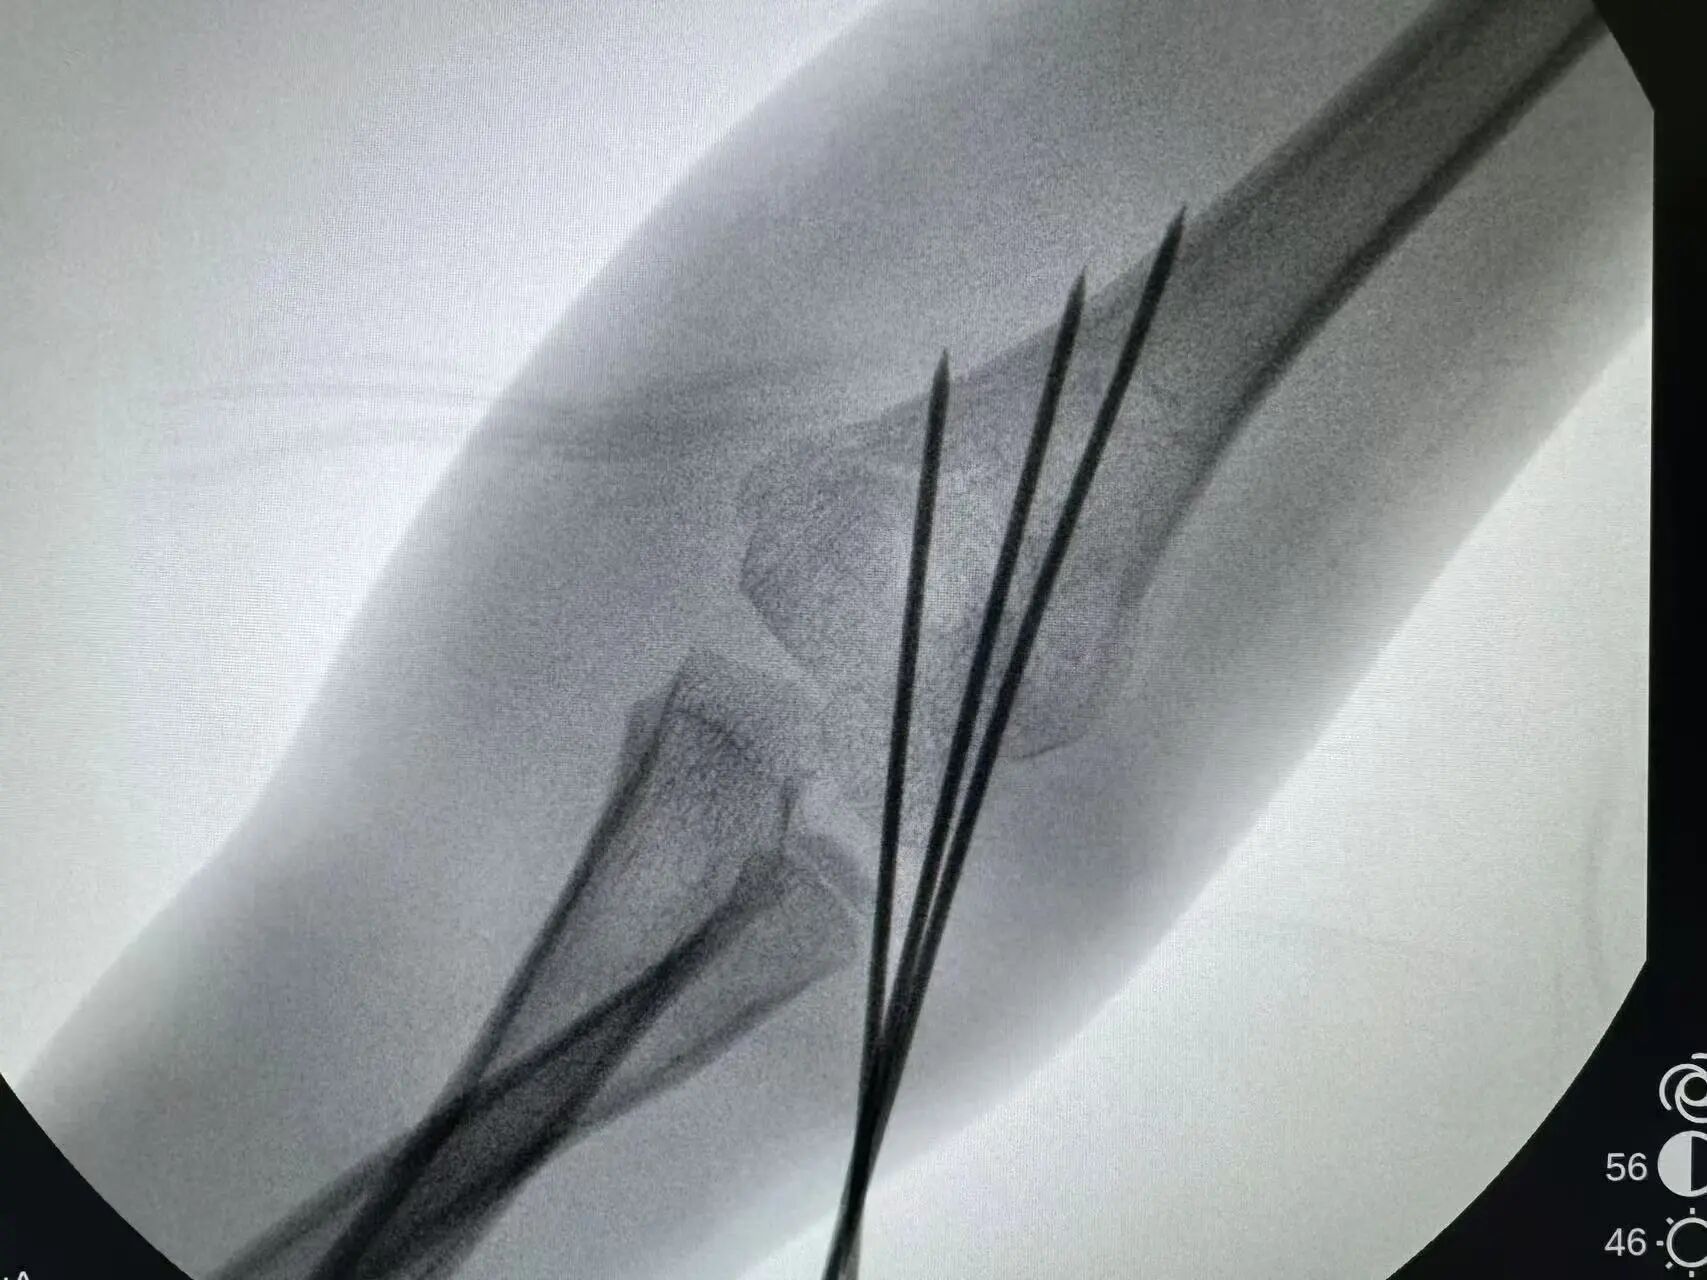

同样“抢时间”的还有小罗和小周的治疗:4岁小罗9月15日深夜入院,10小时后顺利手术;7岁小周同一晚受伤,也在10小时内完成肱骨髁上骨折闭合复位经皮固定术。6岁小郑更是创下“4小时极速手术”纪录——早晨7点40分受伤,8点多入院,11点多手术结束,当天下午就能躺上网课。

“我们的目标是‘24小时内完成急诊手术’,尽量让孩子少耽误一节课。”骨伤科手外·儿骨·烧伤整形组主任陈孝均教授介绍,为了实现这个目标,团队制定了专属流程:孩子入院后,急诊优先开具检查单,放射影像科快速出片;骨科医生同步评估病情,确定手术方案;麻醉科提前做好准备,只要术前检查合格,立刻安排手术——哪怕是深夜或周末,团队也随时待命。